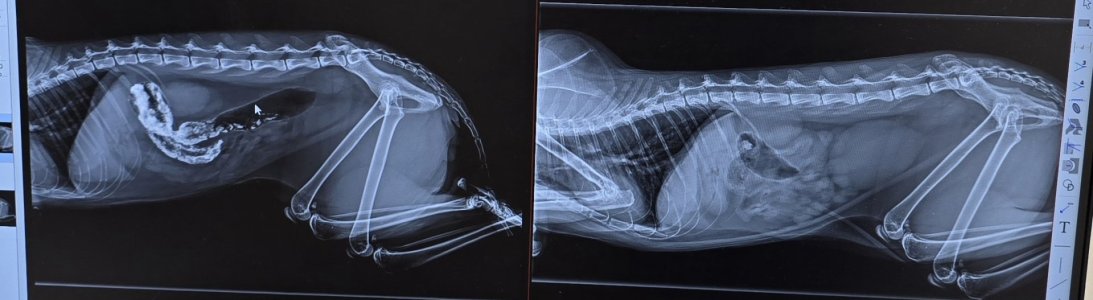

Unbefriedigend ist das Röntgenbild.

Also das eingegebene Kontrastmittel ist nicht komplett durch und Fitz hat bisher keinen Kot abgesetzt.

Hier noch die Röntgenbilder.

Rechts ist das von gestern und links von heute.